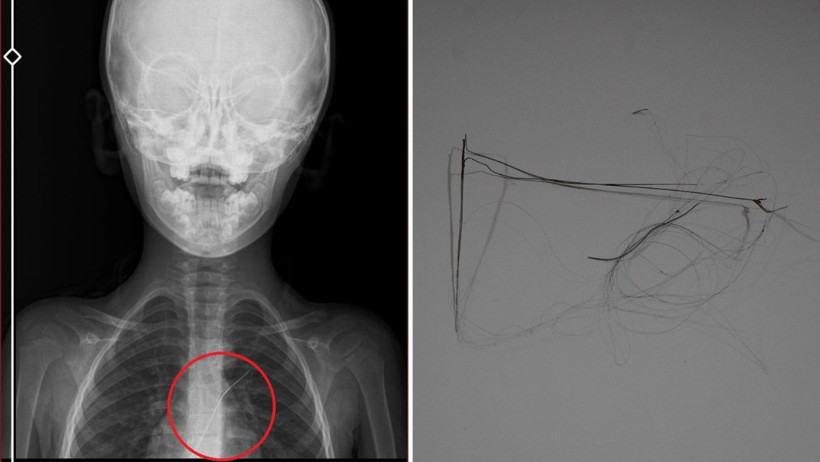

Burada çekilen röntgen ve MR’da Aram’ın vücudunda kateter unutulduğu görüldü. Diyarbakır’daki Gazi Yaşargil Eğitim ve Araştırma Hastanesi Kadın Doğum ve Çocuk Ek Binası’na sevk edilen Aram, 5,5 saat süren riskli bir ameliyata alınarak 18 santimetre uzunluğundaki kateter çıkarıldı. Ameliyat sonrası yapılan incelemelerde kateterin kalp kapakçığına ve ciğerlerine zarar verdiği belirlendi.

Ailenin avukatı Ahmet Yalçın, hastane hakkında hem şikayetçi olduklarını hem de dava açtıklarını belirterek, “Müvekkilim Aram Devran Ötün, 2022 Eylül ayında Dicle Üniversitesi Hastanesi’nde Stevens- Johnson hastalığı nedeniyle tedavi gördü. Tedavi sırasında kendisine kateter takıldı. 18 santimetre uzunluğundadır. Bunu takarken büyük bir ihmalkarlık yapılarak vücudunda unutuldu. Mayıs ayında müvekkilim çok öksürdüğü için Şırnak Devlet Hastanesi’ne kaldırıldı. Burada yapılan tetkiklerde kateterin unutulduğu tespit edildi. Daha sonra Diyarbakır Gazi Yaşargil Kadın ve Çocuk Hastalıkları Hastanesi’ne götürüldü. Çok riskli bir ameliyata alındı ve kateter çıkarıldı. Bu kateterin vücutta yol aldığı tespit edildi. İlk giriş yeri ve çıkarıldığı yer arasında çok fark var ve kalp kapakçığı ile ciğerlerine zarar verdiği tespit edildi. Müvekkillerimin hem maddi hem de manevi zararlarını karşılamak adına Dicle Üniversitesi’ne biz başvuruda bulunduk. 30 günlük cevap süresi içerisinde bize geri dönüş yapılmadı. Biz de maddi ve manevi zararların tazminat için Diyarbakır İdare Mahkemesi’ne davamızı açtık ve sorumlulardan şikayetçi olduk” dedi.

Oğlunun piknikte salatalık parçası yuttuktan sonra sürekli öksürmeye ve kusmaya başladığını söyleyen Semra Ötün, “Çocuğum 3 yıl önce Steven Johnson sendromu hastalığına yakalandı. Milyonda bir görülen antibiyotikten kaynaklı bir hastalık. Doktorlar öyle söyledi. Bizi acilen Diyarbakır Dicle Üniversitesi Çocuk Hastanesi bölümüne sevk ettiler. 1 ay yoğun bakım sürecimiz oldu. 28 gün yoğun bakımda, 3 günde serviste kaldı. Damar yolundan, kasıktan serum taktılar. Kateter denilen tel çocuğun vücudunda bırakılıyor. Biz taburcu olduğumuzda fark edilmiyor. 3 yılın sonunda biz bunu fark ettik. Pikniğe gittik. Oğlum salatalık parçası yuttu ve salatalık parçasından sonra akşama kadar öksürdü. Hiçbir şekilde durmadı. Kusuyordu. Ben şüphelenmeye başladım. Çocuğum normal değildi. Sonra eşime danıştım. Akşam 21.00 civarında acile götürdük. Röntgeni ve MR’ı çekildi. Tuhaf bir şey olduğunu anladık. Doktor röntgeni gösterdi. Tel kalmıştı. Çok kötü bir şekilde. Acil doktoru film çektikten sonra bize bir tel parçasını gösterdi. Bizi bekletmeden Diyarbakır’a sevkimizi verdiler. Diyarbakır Gazi Yaşargil Eğitim ve Araştırma Hastanesi Kadın Doğum ve Çocuk Ek Binası’na gittik. Çocuğun kasıklarından anjiyo yolu ile teli çıkaracaklarını ama riskli bir ameliyat olduğunu söylediler. O süreçte çocuk gerçekten sürekli yoruluyordu. İkide bir oturuyordu. ‘Anne çok yoruldum, karnım ağrıyor’ diyordu. Ben ağrı kesiciler ile geçiştirmeye çalışıyordum. Bu telin 3 yıl boyunca çocuğumda kaldığını öğrendim. Ailece yıkıldık” diye konuştu.